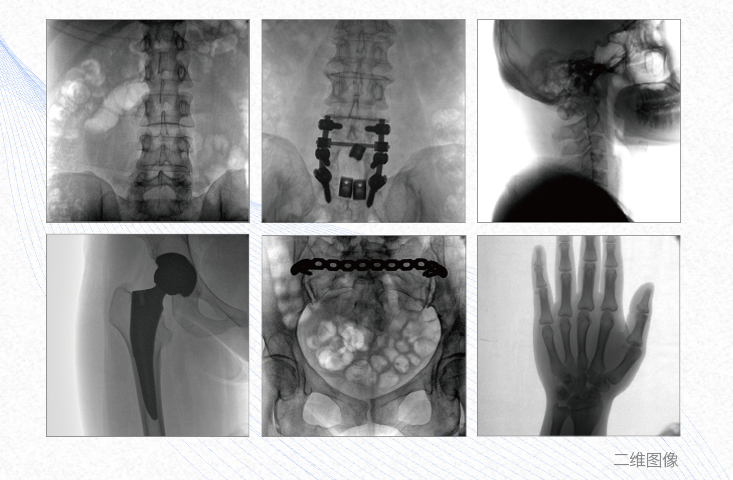

有效重建復雜的脊柱三維模型,提供準確的二維、三維圖像,提高螺釘植入的準確性,縮短手術時間,減少并發癥的概率,降低輻射的攝入。

術中三維成像和橫斷面圖像提供多角度的手術診斷信息,輔助醫生進行術中評估判斷,諸如骨折復位情況和內植入螺釘的尺寸和位置,輔助手術更好地完成。

提供更大的術中三維成像視野,采集更多圖像信息,可一次拍全全段頸椎、全段腰椎、七節胸椎、雙側骶髂關節、股骨頭及單側盆骨。